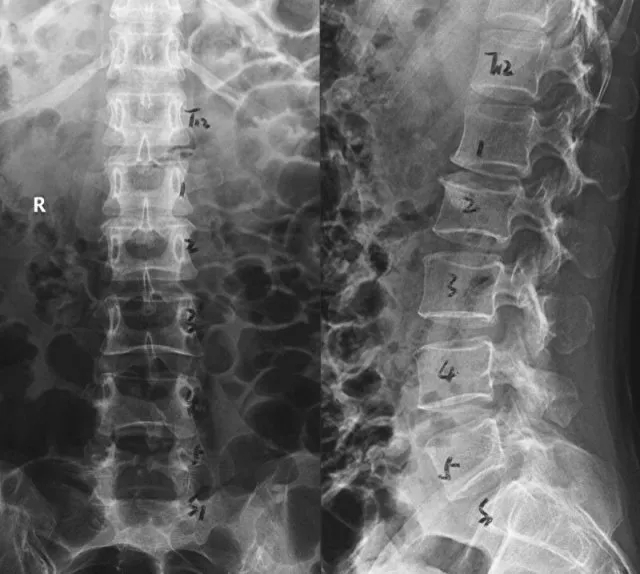

? 術(shù)前正側(cè)位X線片

入院時(shí),患者臥床不能自理,雙下肢劇烈疼痛讓患者連續(xù)幾個(gè)晚上睡覺(jué)都十分困難。查體顯示雙側(cè)髂腰肌肌力II級(jí),雙側(cè)股四頭肌力III級(jí),遠(yuǎn)端肌力輕度減低。鞍區(qū)感覺(jué)減退,肛門(mén)括約肌輕度松弛,小便費(fèi)力。綜合影像學(xué)檢查結(jié)果診斷為腰1/2椎間盤(pán)脫出,馬尾綜合癥。6月25日,在空軍軍醫(yī)大學(xué)西京醫(yī)院脊柱外科王哲主任安排下,丁坦副教授主刀實(shí)施腰1/2椎板切除減壓,髓核摘除,椎間植骨融合內(nèi)固定術(shù),手術(shù)用時(shí)2小時(shí)順利結(jié)束。